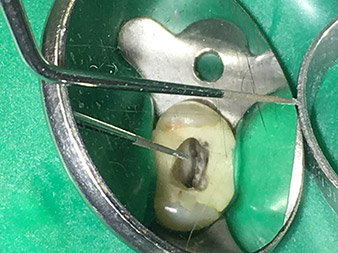

Die Spitze 4E - dieses Instrument eignet sich optimal zum Präparieren des Kavitätenbodens beim Übergang zu den Kanälen. Hier kann der Übergang Kanal - Kavitätenboden optimal abgerundet werden, sodass ein Trichter im Kanal entsteht.

Zusätzlich ist das Instrument die ideale Wahl, wenn es um das Freilegen der Kanäle von Dentinüberhängen geht. Insgesamt kann die Kavität mit dieser Spitze sehr effektiv und minimalinvasiv präpariert werden, indem Überhänge, Ecken und Kanten optimal abgerundet und geglättet werden.

Dr. Nouraie: Der Einsatz von Ultraschallspitzen ermöglicht einen gezielten, schonenden und minimalen Substanzabtrag an der gewünschten Stelle (wie z.B. bei der Freilegung der Kanaleingänge, beim Abrunden des Kavitätenbodens und Freipräparieren von abgebrochenen Instrumenten oder Stiften sowie beim Bearbeiten der koronalen Kanalabschnitte).

Die Glättung und Abrundung der Kanalübergänge kann gezielter erfolgen als mit Hilfe von Bohrern. Insbesondere die Aktivierung der Spülflüssigkeit bringt enorme Vorteile, die durch andere Instrumente nicht gewährleistet werden kann. Mit Hilfe der Spezialinstrumente von W&H können ganz neue Indikationen minimalinvasiv durchgeführt werden, wie z.B. eine Revision von abgebrochenen Spitzen und Stiften.